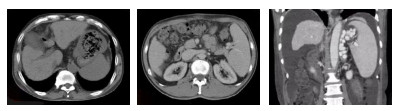

2 结果 2.1 CTP与胃镜表现CTP均提示有肝硬化,52均存在食管胃底静脉曲张,其中单纯食管静脉曲张12例,单纯胃静脉曲张6例,CTP提示食管静脉曲张造影剂外溢6例,与胃镜检查结果一致。胃镜考虑食管胃底静脉曲张(esophagogastric varices,EGV)破裂出血45例,其中食管静脉曲张发现出血或血栓头36例,距门齿28 cm以上2例,28~32 cm 13例,32 cm至齿状线21例,3个位置比较有显著性差异(P < 0.05),胃底静脉曲张发现出血或血栓头9例(其中食管胃底均发现出血或血栓头3例);门高压性胃病(portal hypertensive gastropathy,PHG)出血4例,消化性溃疡(peptic ulcer,PU)出血3例,其中胃溃疡出血2例,十二指肠球部溃疡出血2例。CT提示胃腔大量血液残留22例,16例在常规左侧卧位胃镜操作无法暴露出血病灶,由于有大量血凝块与食物残留,采用改变体位的方法暴露病灶后给予有效止血处理。(见图 1、图 2)。

| 图 1 CTP显示矢状位、冠状位提示胃腔大量血液残留、存在门体分流 |